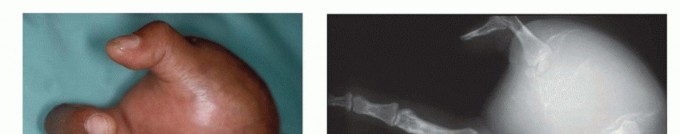

FIG 3 • A. Clinical picture and (B) plain radiograph showing high-grade sarcoma of the first metacarpus. C. Fungating soft tissue sarcoma of the hand. D. Extensive necrotic and fungating sarcoma of the wrist. These tumors necessitate below-elbow amputation to achieve local tumor control.